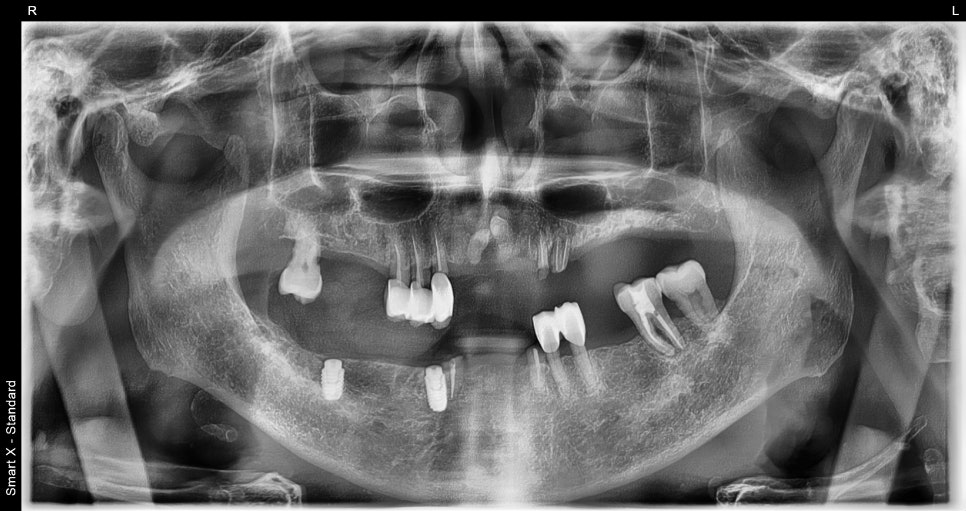

Comparison Before and After Treatment

※ The photos below are before-and-after comparison photos.

– Appearance after upper complete denture placement

– Appearance after lower implant placement and partial denture placement

<Before>

<After>